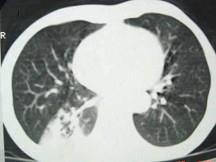

问题 男,40岁,胸背疼痛一周,消瘦一月,CT检查如图,最可能的诊断为 ( )

选项 A、右下肺肺泡癌 B、右下肺炎性假瘤 C、右下肺脓肿 D、右下肺炎 E、右下肺结核

答案 A